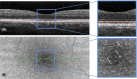

Purpose: Numerous small hyperreflective dots (HRDs) can be seen within the hyporeflective layer between the ellipsoid zone (EZ) and the interdigitation zone (IZ) on C-scan spectral-domain optical coherence tomography (SD-OCT) with a yet unknown variation under light conditions. The aim of this study was to explore light-induced SD-OCT changes in these HRDs.

Results: Twenty healthy volunteers were prospectively included. The number of HRDs differed significantly over time (p = 0.0013). They decreased in Group 1 after dark adaptation and retinal photobleaching before returning to baseline levels 30 min later; conversely, they remained relatively constant in Group 2 throughout the study (p < 0.001). Light-skinned subjects had less HRD than dark-skinned subjects.

Conclusion: We observed light-induced modifications in the space between the EZ and the IZ. We hypothesize that the HRDs visible in this zone correspond to melanosomes that are mobilized during the light stimulation protocol. Larger studies are recommended to further evaluate and confirm light-induced SD-OCT changes under physiological and pathological conditions.